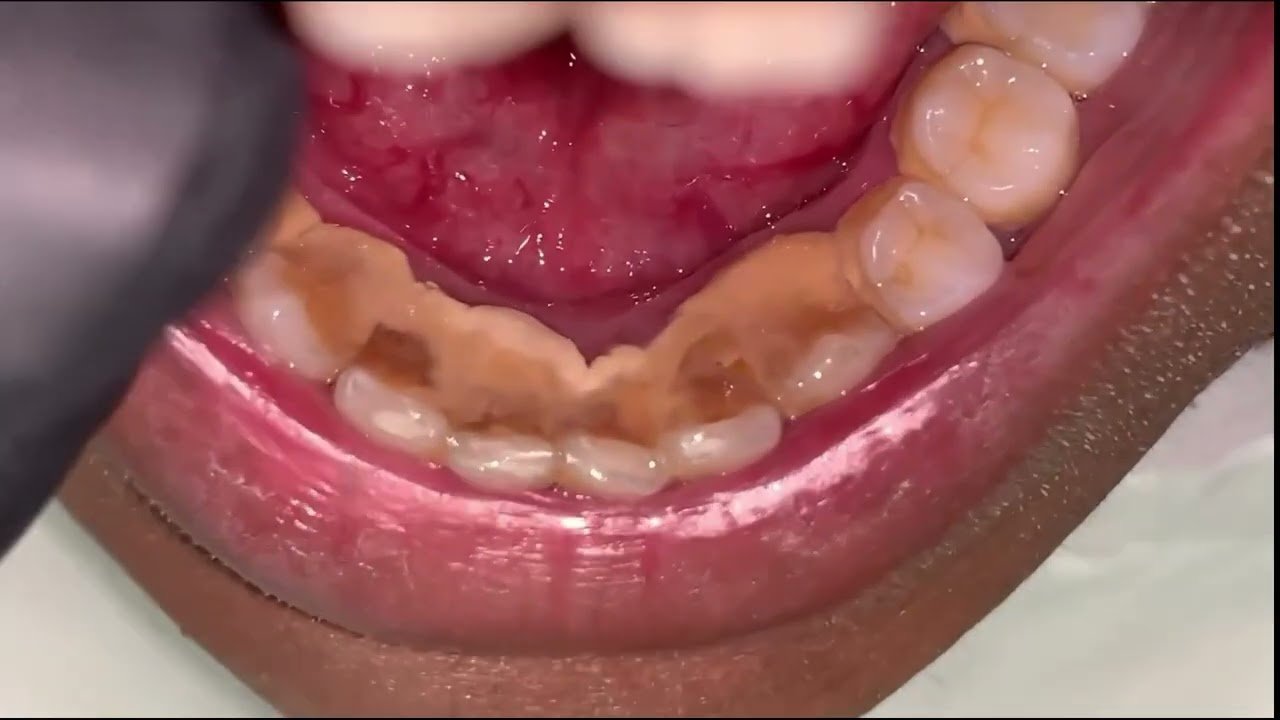

Cómo Curar la Gingivitis Rápido: Guía Completa

El Mejor Cepillo de Dientes para Combatir la Gingivitis: Guía Completa